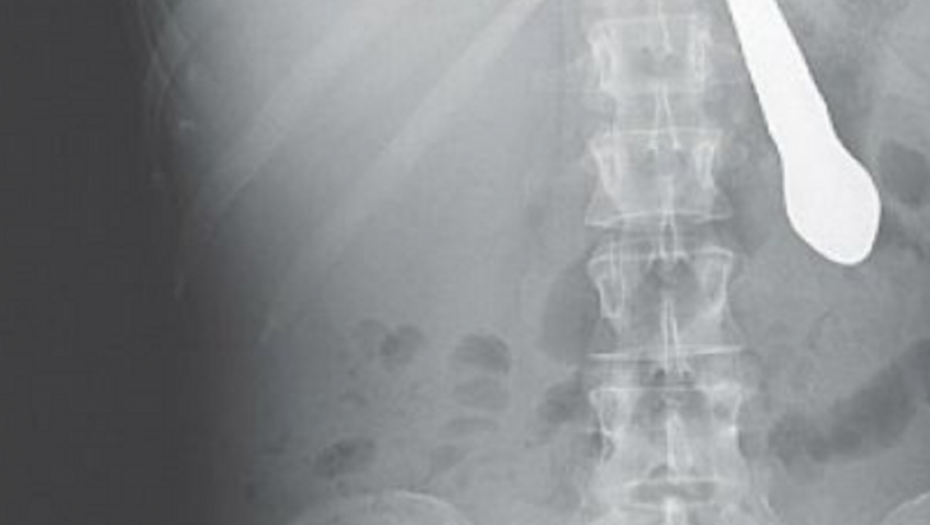

Progutao nož od 25 centimetara!

Pacijent negirao uzrok tegoba koji je otkriven snimkom na CT skeneru i sasvim normalno se ponašao. Na hirurškom odeljenju Opšte bolnice "Dr Radivoj Simović" u Somboru preksinoć se pojavio pacijent sa žalbama na bolove u grlu i otežano disanje, kod kojeg je otkriveno da je progutao nož od 25 centimetara!

Nož s drškom okrenutom prema želucu, probio je jednjak pacijenta, koji ni prilikom dolaska u bolnicu, a ni kasnije kad je CT skenerom utvrđeno šta je uzrok njegovih tegoba nije hteo da prizna da je bilo šta progutao.

"Pacijent se javio na Grudno odeljenje odakle je upućen na Hirurgiju. Specijalizant koji je bio dežuran pozvao me je da od kuće dođem u bolnicu. pošto sam pregledao pacijenta procenio sam da nema potrebe za drenažu grudnog koša, koji je pregledao pneumoftitiolog s Odeljenja za plućne bolesti. Uputio sam ga na skener gde je utvrđeno da se u njegovom jednjaku nalazi nož", kaže hirurd dr Zoran Parčetić, načelnik odeljenja za prijem, trijažu i zbrinjavanje urgentnih stanja u somborskoj bolnici.